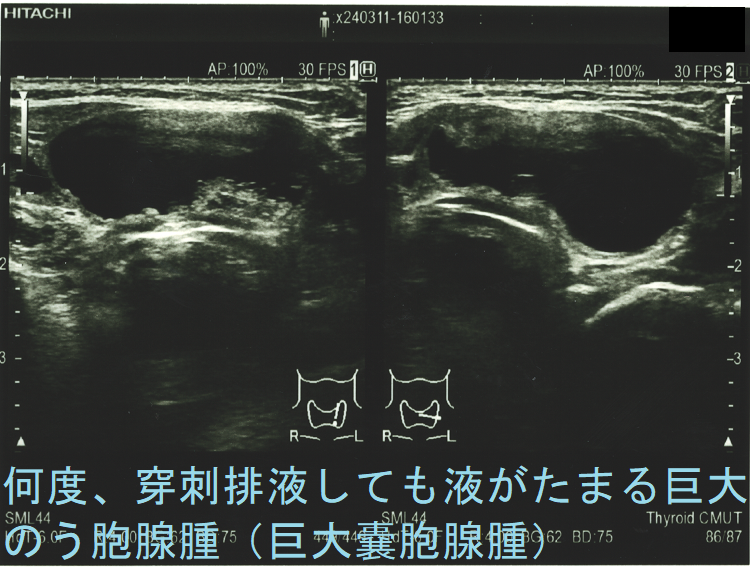

頻回に穿刺排液しても液がたまる巨大のう胞腺腫(巨大嚢胞腺腫)は、良性腫瘍(のう胞型濾胞腺腫:嚢胞型濾胞腺腫)であっても手術適応になります。単に、のう胞(嚢胞)と呼ばれる事も多いですが、甲状腺組織の破壊・変性によるのう胞変性(嚢胞変性)でなく、れっきとした腫瘍です。

岩手県立中央病院の報告;97 x 71 x 60 mmの巨大な甲状腺のう胞腺腫(甲状腺嚢胞腺腫)で、排液後1週間以内に液が再貯留し始めたため、甲状腺半葉切除したそです。病理標本では、のう胞周囲は炎症が強く、炎症性浸出液の可能性が考えられます。(第57回 日本甲状腺学会 P2-070 巨大な甲状腺嚢胞により経口摂取困難となった一例)

ケース⓪ 巨大のう胞腺腫(巨大嚢胞腺腫) 気管圧排

ケース① 巨大のう胞腺腫(巨大嚢胞腺腫) 7 cm以上

ケース② 巨大過ぎる甲状腺のう胞腺腫(甲状腺嚢胞腺腫) 8 cm以上

ケース⑥ 両側性の甲状腺のう胞腺腫(甲状腺嚢胞腺腫)が気管を圧迫